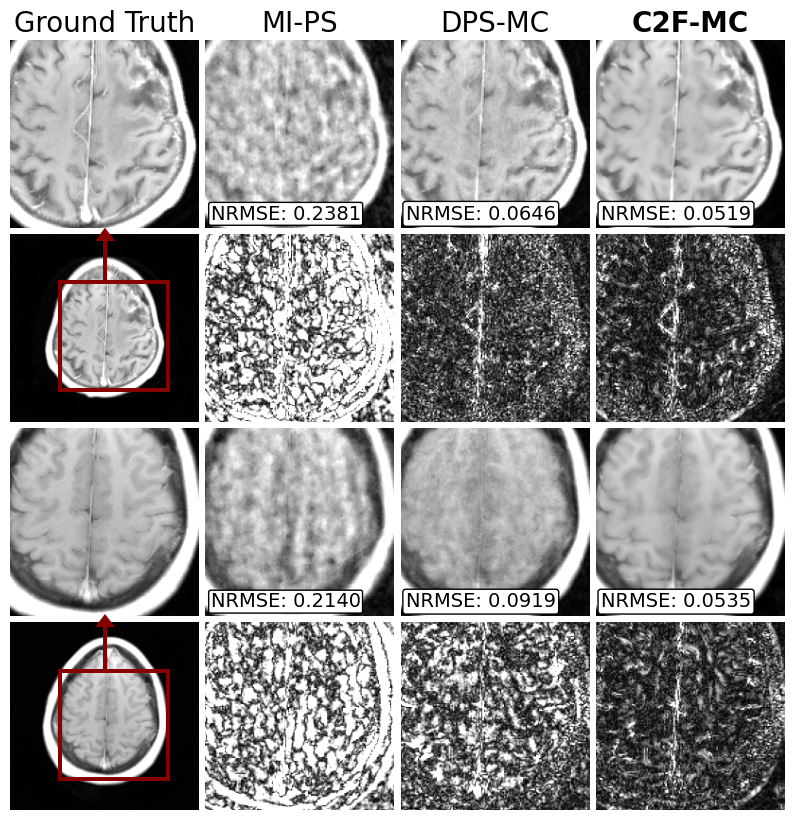

Fig. 3: Non-rigid motion correction and reconstruction on multicoil data with 8 simulated motion states each undersampled by 64x. Error x10 is shown below each image. Our method (C2F-MC) outperforms the same method using standard diffusion (DPS-MC) and the state-of-the-art rigid motion correction (MI-PS).

4.1 Non-rigid simulated motion correction

We test our method under the disjoint 2D sampling regime, designing 𝐌\mathbf{M} to collect just 1/8 of kk-space. However, we introduce 8 different motion states; thus, each 𝐌(τ)\mathbf{M}^{(\tau)} has an acceleration of 64x, with a maximum displacement of at most 15 pixels. Results are shown in Fig. 3. We compare our results (C2F-MC) to the same method on a standard diffusion model (DPS-MC) and the state-of-the-art rigid motion correction (MI-PS). Both C2F-MC and DPS-MC used 10 alternating minimization iterations during inference, uniformly across the sampling process.

Our method outperforms all methods, demonstrating the effectiveness of coarse-to-fine denoising compared to standard diffusion methods. There is less hallucination and missing reconstruction details compared to the other methods. Furthermore, we perform better than MI-PS, as its rigid motion assumption does not generalize to non-rigid motion.

Test Statistics: Over 100 simulated non-rigid motion-corrupted images, the NRMSE (Normalized Root Mean Squared Error) statistic of C2F-MC was 0.058 ±\pm 0.0032.